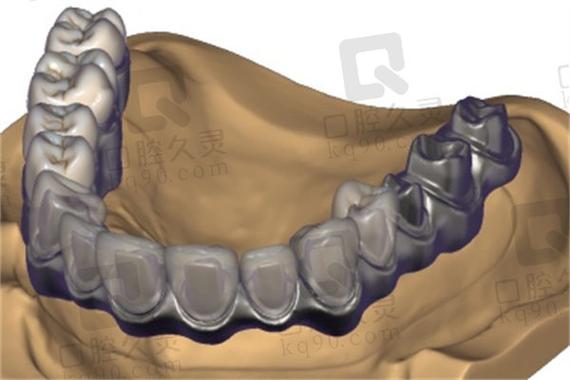

对于全口或半口牙缺失患者,All-on-4/6技术结合种植桥架可实现“当天种植、当天戴牙”的即刻负重效果,该技术通过植入4颗(All-on-4)或6颗(All-on-6)种植体,利用钛合金或氧化锆桥架将种植体连接成整体,上部制作固定义齿,即刻恢复患者咀嚼功能,桥架在此类修复中需具备极高的整体强度和抗变形能力,以支撑全口义齿的长期使用,数字化技术的应用(如术前CBV规划、3D打印桥架)可确保种植体位置精准,桥架与颌骨贴合度达95%以上,大幅提升手术效率和修复效果,尤其适用于希望快速恢复生活质量的患者。